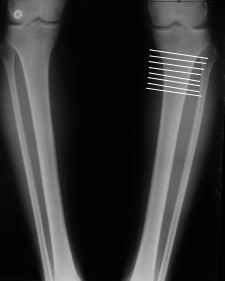

AC> Обратилась дама 25 лет. Вынуждена ходить в брюках из-за genu varum,

AC> что побудило обратиться за коррекцией.

Сейчас это модно (в смысле косметическая коррекция)... Хотя, судя по фото - в данном случае енто вполне оправдано...

Судя по снимку у девушки имеется внутренняя установка надколенников...

Как у нее с торсионным статусом? Бедро? Голень? КТ? Торсиометры? А то, куда будут

смотреть надколенники после вашей коррекции - тоже существенный

косметический момент. Или не так?